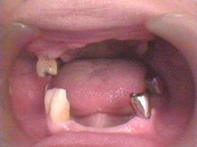

| | | 上顎が右上がりになっています。顔を傾けているわけではありません。合わない入れ歯を長期使用することで骨が変形してしまいます。下顎は比較的きれいな骨状態を維持しています。 |